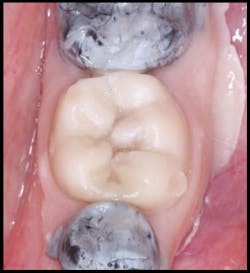

Figure 7: The silicone matrix was removed immediately after polymerization.

All excess material was removed, and occlusion was checked. The restoration was coated with EQUIA Coat and then light cured. The final result had ideal contours and occlusion (figure 8). At a 23-month recall visit, the tooth was still in occlusion, and minimal wear was noted (figures 9 and 10).

Figure 8: The final result